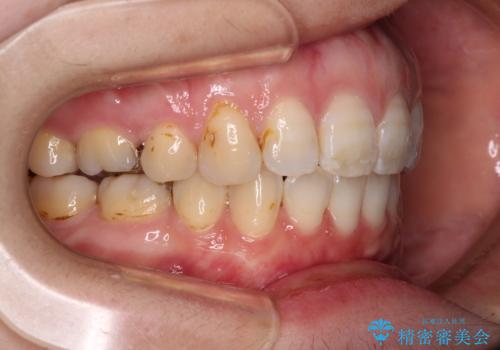

積極的に前歯を牽引したことで、口元の閉じにくさは顕著に改善され、横顔のシルエットが大幅に変化しました。

- 口元の閉じにくさと、前歯のでこぼこの歯並びを気にして来院された患者様です。

口元を積極的に引っ込めるために、上下左右の小臼歯計4本を抜歯することとしました。